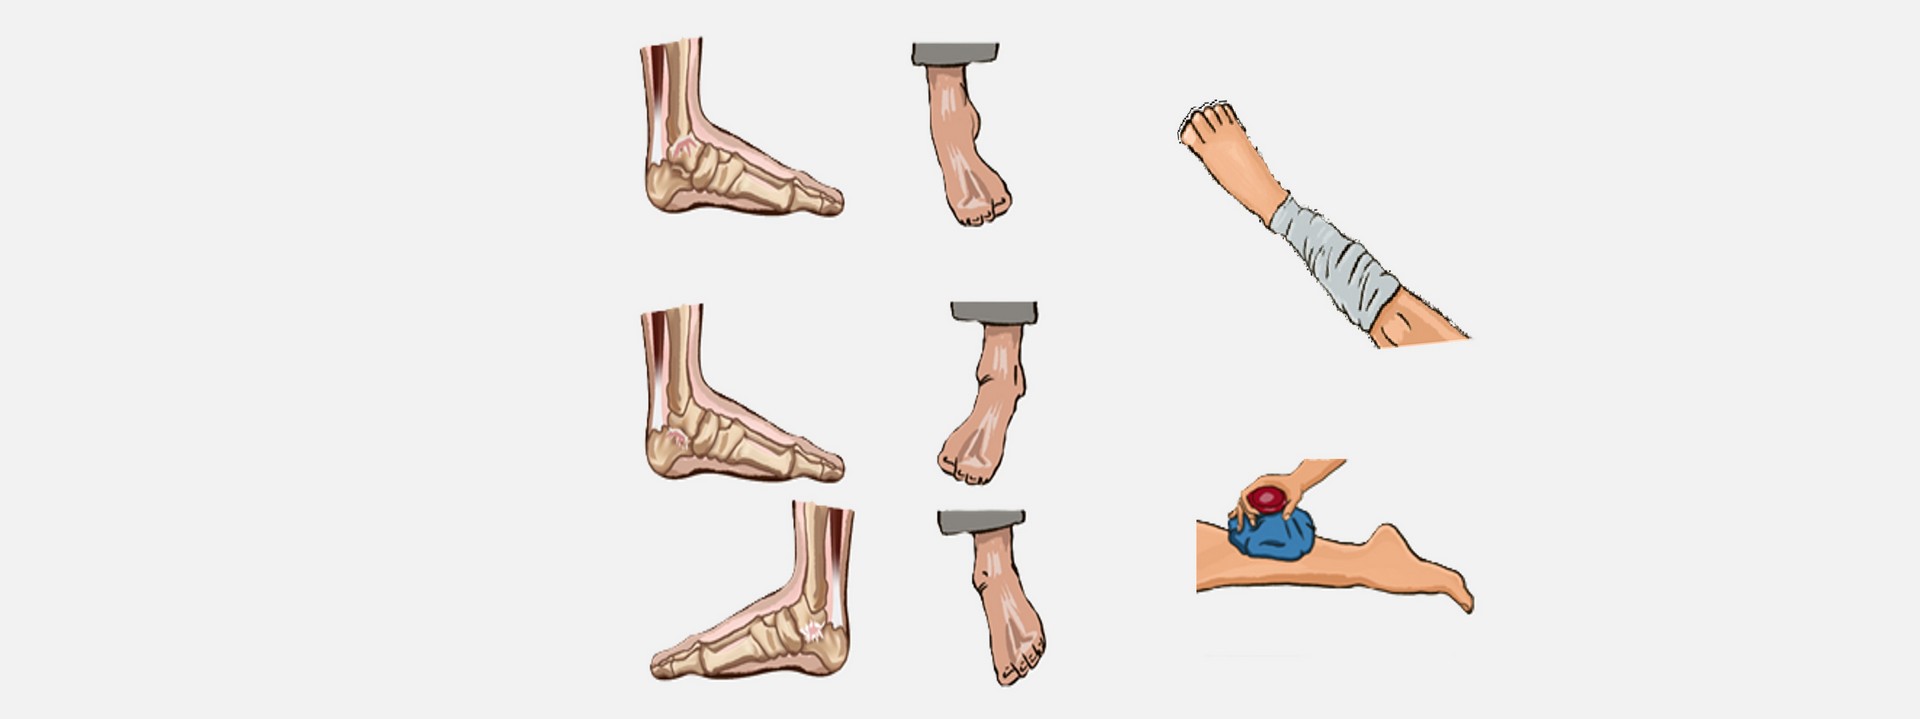

Θλάση & Διάστρεμμα

Συμπτώματα:

- Έντονος πόνος

- Οίδημα

- Περιορισμένη κινητικότητα

Πρώτες Βοήθειες:

- Παύση δραστηριότητας & κλήση 112/166

- Εφαρμογή ψυχρών επιθεμάτων για 20-30΄ανά εφαρμογή

- Εφαρμογή συμπιεστικού επιδέσμου